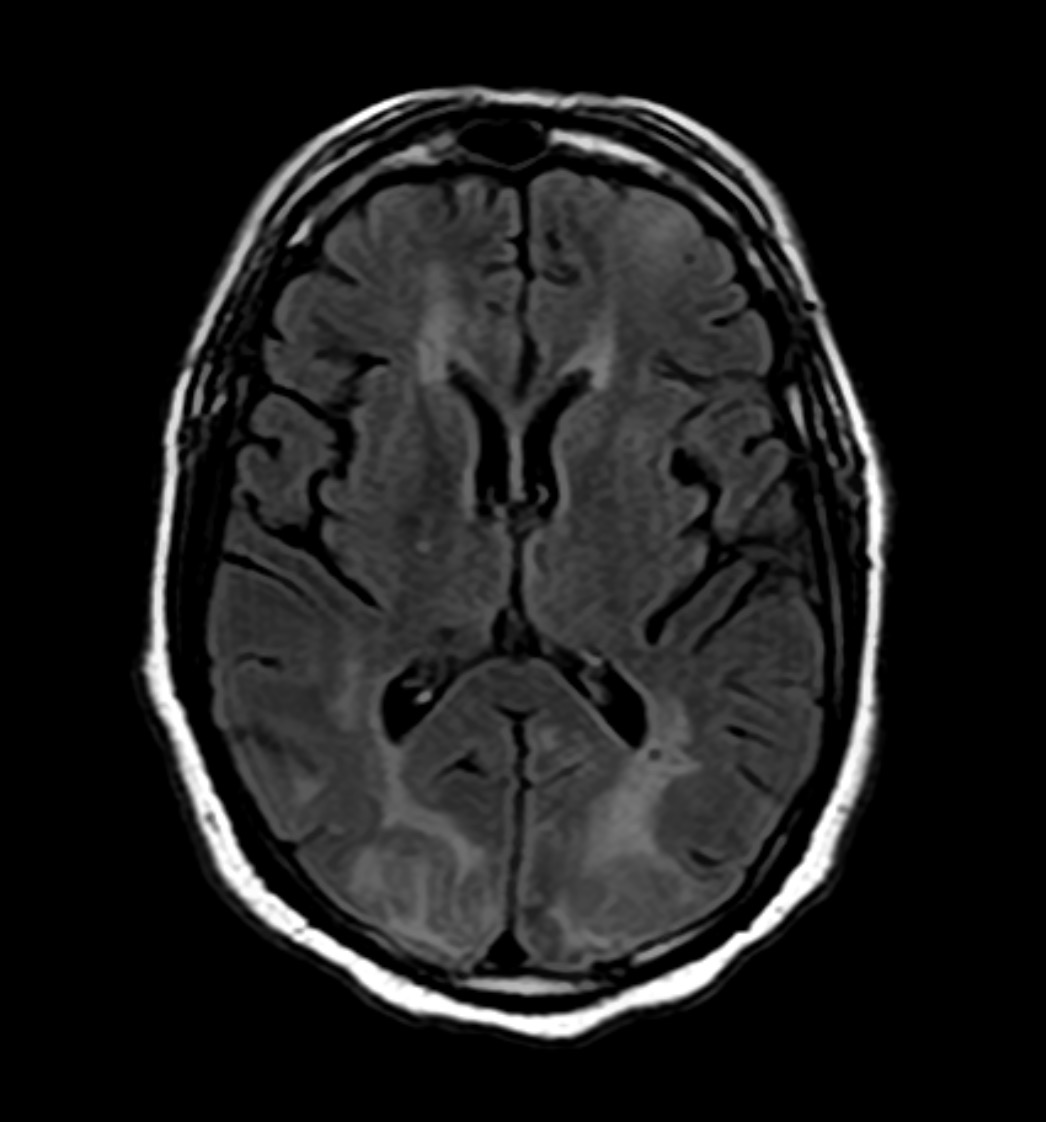

MRI provides high-resolution images using magnetic fields and radiofrequency pulses, making it the modality of choice for most neurological diseases.

Key Sequences:

T1-weighted: anatomy, structural detail, post-contrast imaging

T2-weighted: edema, inflammation, and demyelination

FLAIR: suppresses CSF to highlight periventricular lesions (e.g., MS)

DWI/ADC: detects acute ischemia

SWI: sensitive to blood products and calcification